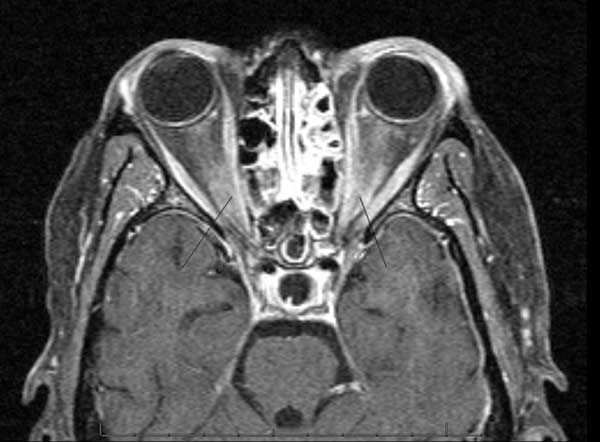

Initial lumbar puncture disclosed a high opening pressure (34 cm H2O) and CSF with 16 white blood cells (91% neutrophils and 9% lymphocytes), normal glucose level, and protein level of 74 mg/dL. Results of a VDRL test, a Cryptococcus antigen test, an acid-fast stain, a Mycobacterium tuberculosis polymerase chain reaction (PCR) assay, and all cultures (viruses, fungi, bacteria, and mycobacteria) were negative. A CT scan of the brain with contrast showed mild atrophy, but an MRI scan showed diffuse enhancement of the bilateral optic nerves (Figure).

Figure. This axial T1-weighted MRI scan after intravenous injection of gadolinium shows marked signal enhancement of both optic nerves, indicating disruption of the blood-nerve barrier and optic neuritis.